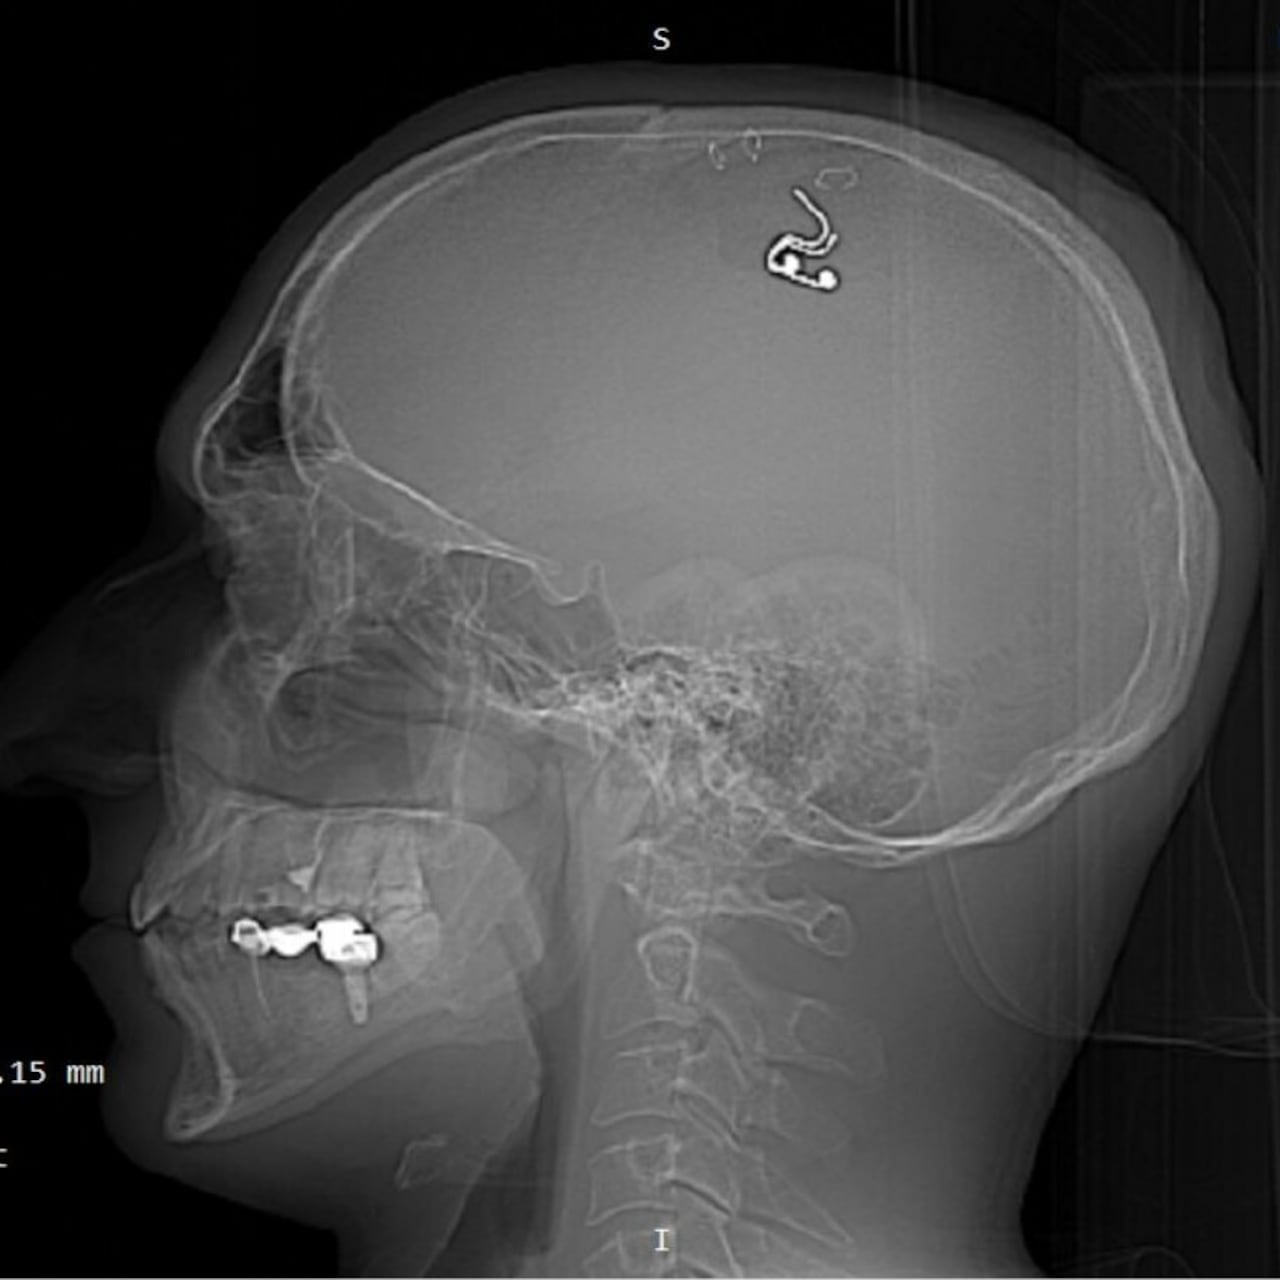

A pesar de no tener ningún tipo de conocimiento sobre la medicina en general y especialmente en lo relacionado con la neurociencia, el hombre decidió someterse a un procedimiento para perforarse la cabeza, implantarse un chip y así lograr controlar sus sueños mediante una estimulación electrónica.

A diferencia de lo que muchos pensarían, Raduga se realizó él mismo el procedimiento con un taladro que compró en una ferretería, según contó. En su cuenta de Twitter, el sujeto publicó unas fotos con las que confirmó que se practicó la perforación en su propia casa el 17 de mayo de 2023, lo que lo llevó a perder un litro de sangre.

Tras esta preparación, el ruso se perforó la cabeza y logró implantarse el chip en el cerebro. Sin embargo, cinco semanas después un grupo de trabajadores de la salud se lo sustrajeron y le advirtieron de los riesgos que corrió y que podría volver a tener, si intenta algo parecido nuevamente. “Terminé la cirugía, me duché y trabajé durante 10 horas seguidas. La gente no sabía absolutamente nada”, dijo.